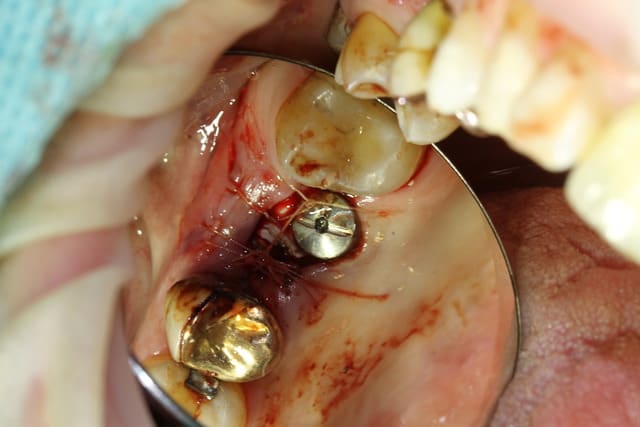

extract récente implant + Vitalos

quand tu fais une photo avec miroir, xavier, ne prends QUE le miroir...ou recadre avec ton logiciel de retouche photo

et pendant que tu es dans ce logiciel de retouche, tu en profites pour retourner l'image à 180° et faire un "mirroring" qui te permets de retrouver l'image telle qu'elle aurait du être avec une vue "direct"...;-)

comme tu peux le constater, une photo du miroir te donne une profondeur de champs incroyable...tout simplement parce que tu photographies une image "plate" et non un objet en 3D...;-)

en gros, comme çà...çà m'a pris 1 minute...